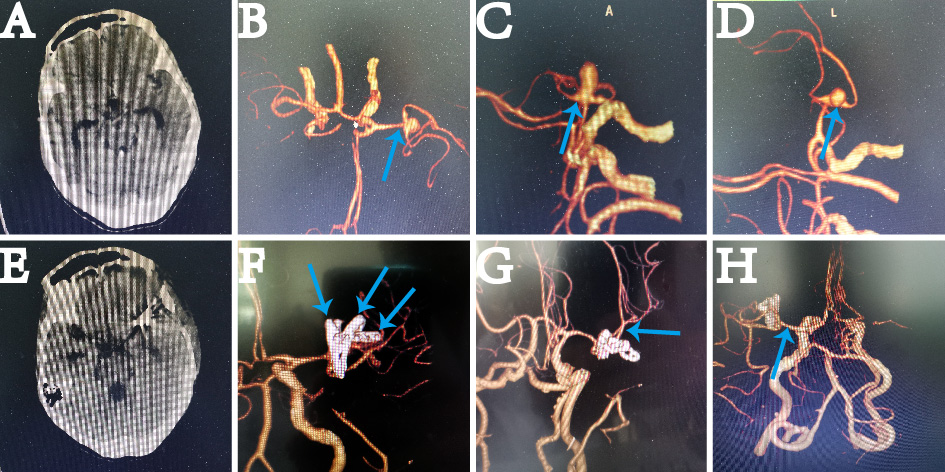

女性,70岁,以“突发头痛、头晕,四肢乏力3天”入院。入院时神经系统查体:呈嗜睡状态,颈强。入院时头部CT、CTA示:左侧大脑中动脉动脉瘤(第一分叉处)(Figure 1)。

Fig 1: A-D为术前CT及CTA;E-H为本次术后CT及CTA(蓝箭头显示载瘤动脉远近端、动脉瘤颈、动脉瘤顶、三枚动脉瘤夹)

患者术后意识逐步恢复,四肢运动正常。术后CT无梗塞,CTA示:动脉瘤夹闭完整,载瘤动脉远近端无狭窄。(Figure 1:E-H)其余神经功能与术前无变化。